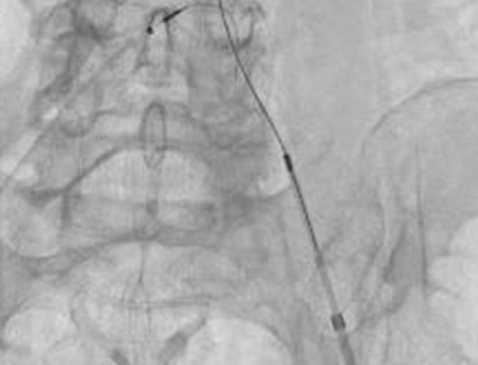

Computed tomographic (CT) angiography of the left lower extremity showed total occlusion of the proximal left common iliac artery (Fig. 1). Initially, we performed intra-arterial thrombolysis with urokinase 200,000 units for 1 hour. Follow-up angiography revealed antegrade flow with large residual thrombi (Fig. 2), so we decided to perform a percutaneous mechanical thrombectomy through the ipsilateral femoral artery using the OASIS™ thrombectomy system (Medi-Tech/Boston Scientific, Watertown, MA) (Fig. 3). Immediate post-procedural angiography demonstrated almost complete patency of the previously occluded artery. Follow-up CT angiography 14 days later showed a normal left common iliac artery (Fig. 4).